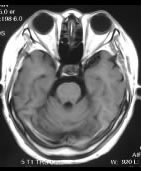

75歳 女性 正常例